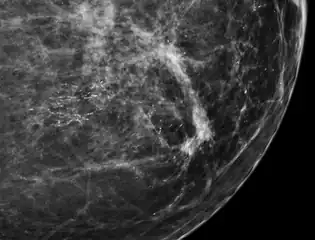

They can be scattered throughout the mammary gland, or occur in clusters. Microcalcifications can be an early sign of breast cancer. Based on morphology, it is possible to classify by radiography how likely microcalcifications are to indicate cancer. [2]

In breast